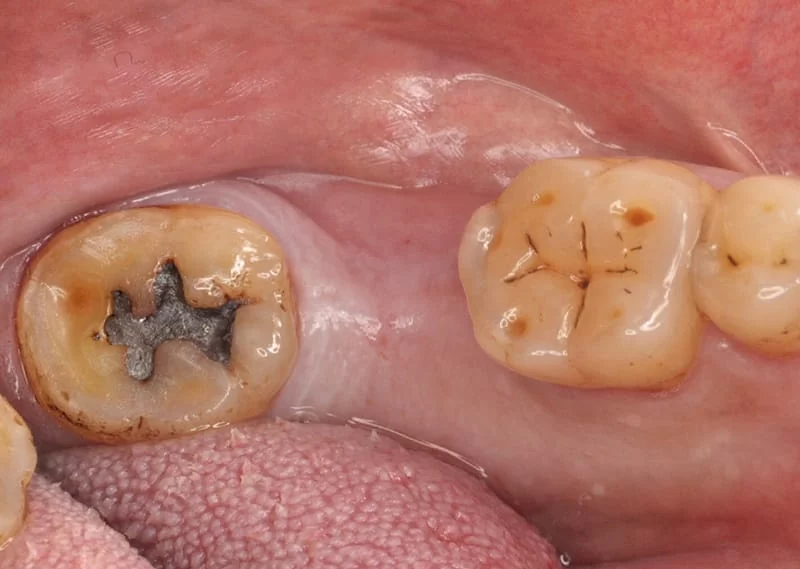

- 入人工牙根(進行植牙第一階段及第二階段)。<圖二~圖五>

植牙前 <圖二>